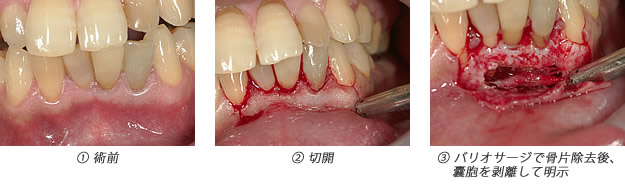

歯内療法か?外科的療法か?病理組織的には病変に上皮があれば歯根嚢胞(外科的療法必要)、上皮がなく繊維と血管だけの場合は歯根肉芽腫(歯内療法で治癒可能)と呼ばれますが、実際の所レントゲン(CTを含む)で判断するのは困難です。臨床の現場ではまず歯内療法のみを選択しますが、治癒しない場合は外科的療法(嚢胞摘出&歯根端切除術)に移行するといった流れになることが多いです。 |